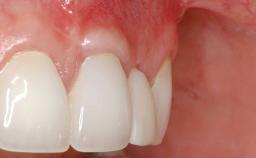

Paolo Casentini demonstrates that peri-implantitis can be successfully treated even at an advanced stage. He discusses a case in which the existing implants and prostheses were both retained while regenerating the defect and creating a band of keratinized tissue. A 69-year-old female patient was referred by her general dentist for evaluation of a recurrent infection at previously placed and restored implants in the posterior left mandible. The patient’s chief complaint was recurrent swelling and pain in the molar region of the left posterior mandible with discomfort during brushing in the same area. The patient reported receiving two implants (36 and 37) nine years earlier.